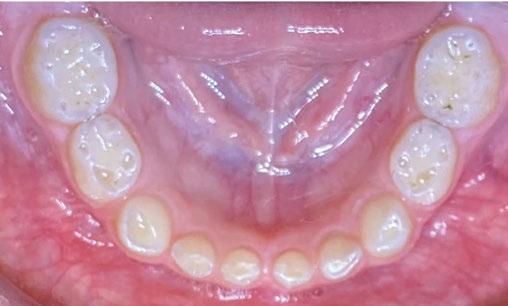

The following procedures were accomplished under general anesthesia on an outpatient basis — full mouth dental radiographs and a comprehensive oral exam. A complex odontoma was found to be the etiology of the noneruption of the maxillary right permanent central incisor (Figure 2). Since dental caries also was diagnosed, a full-mouth prophylaxis was completed. Dental caries was controlled, and teeth were restored. A 5 mm incision was made on the gingiva over the impacted maxillary right permanent central incisor, and two tooth-like structures were extracted from the right maxillary incisor area. A postoperative periapical radiograph was taken to confirm complete odontoma removal (Figure 3). Three interrupted sutures using 3-O chromic gut were placed.

Figures 2 and 3: 2. Periapical radiograph of involved area taken in the operatory during initial dental rehabilitation under general anesthesia (left). 3. Periapical radiograph of involved area taken in the operatory during initial dental rehabilitation under general anesthesia immediately after odontoma removal (right)